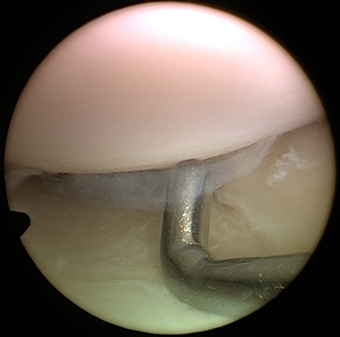

We continue to recruit patients for this clinical trial based in Chester (please see a list of Inclusion and Exclusion Criteria). The BioPoly™ first implantation was done early in January 2012 by Mr Dinesh Nathwani at the London Clinic (for more information please see the article from The Telegraph and the article from Mail Online). The first large BioPoly (the "racetrack", picture above) was implanted in April 2012 by Mr Mike McNicholas, at the Warrington Hospital. So far we have implanted 22 BioPoly implants, with good short to mid term functional results.

Pinterest Arthroscopic and MR Image Boards

We are posting a selection of original arthroscopic and MR images from our daily clinical and surgical practice on Pinterest and Twitter. All images are anonymous and are intended to provide good quality visual information on typical knee problems but also normal knee anatomy for educational purposes. We will aim to Tweet a few selected images from time to time but all images will be available on Pinterest Arthroscopy and MRI boards. We are still thinking about posting some images on Instagram. Please let us know your thoughts (office@kneeclinic.info).